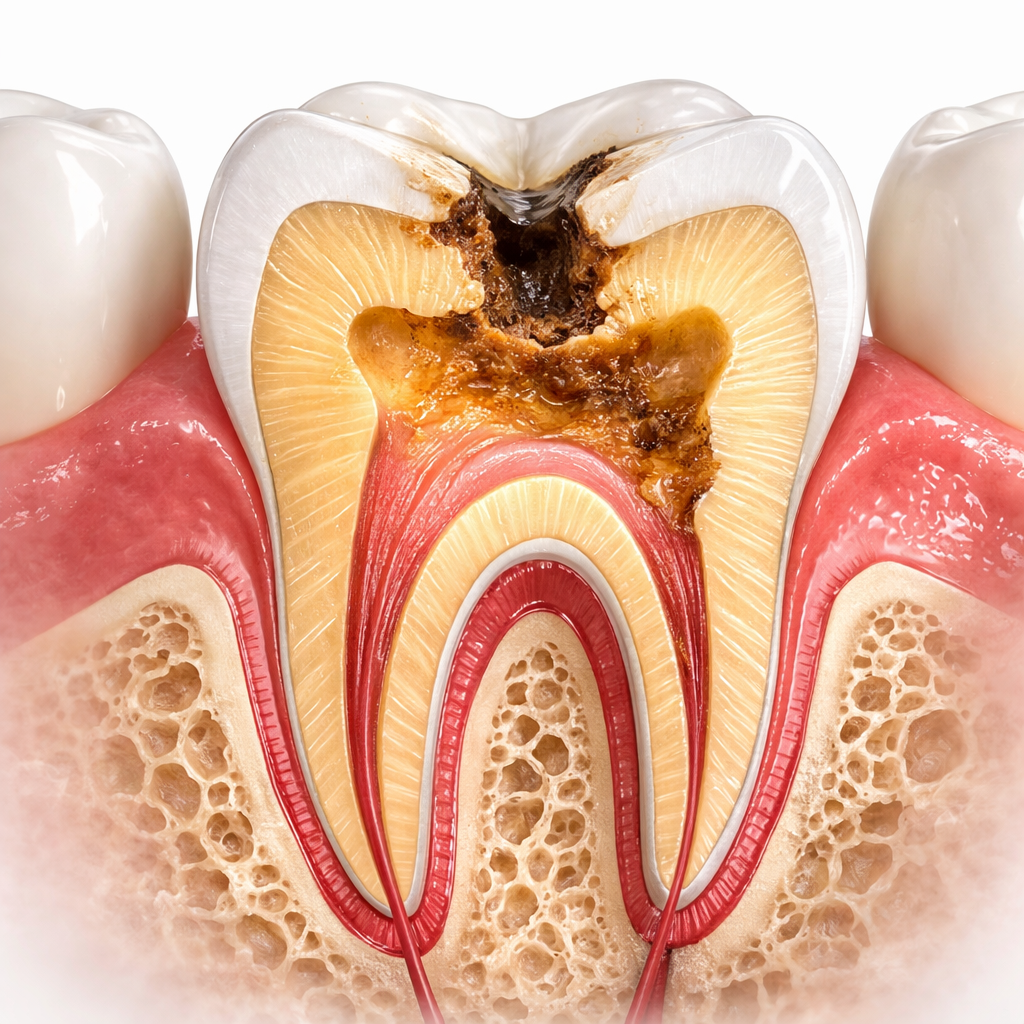

السن لا يتكون من طبقة واحدة فقط. بعد المينا تأتي طبقة العاج، ثم اللب في الداخل، وهو الجزء الذي يحتوي على الأعصاب والأوعية الدموية. لهذا السبب يصبح الألم أوضح عندما يصل التسوس إلى طبقات أعمق، لأن الضرر هنا لم يعد سطحياً فقط، بل بدأ يقترب من الجزء الحساس من السن، مما قد يستدعي تدخلاً دقيقاً مثل علاج قناة الجذر للأسنان.

4) تسوس اللب أو التسوس القريب من العصب

هذه مرحلة متقدمة يصل فيها التسوس إلى الأنسجة الداخلية الرخوة في مركز السن. هنا قد يصبح الألم مستمراً أو شديداً، وقد تظهر علامات التهاب أو خراج. وعند رؤية صورة سن في هذه المرحلة، قد يبدو التجويف كبيراً أو قد يظهر تكسر في بنية السن، لكن التشخيص النهائي يعتمد على الفحص والأشعة وليس على المظهر فقط.